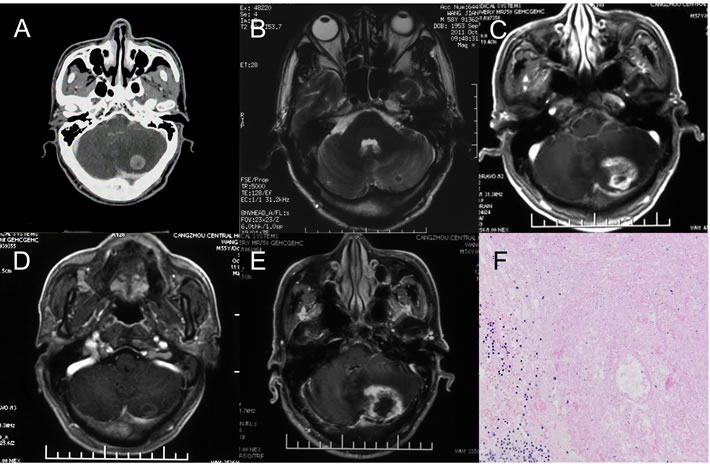

Data for 1 patient was used to further develop an in-depth understanding of radiation brain necrosis recurrence following bevacizumab discontinuation. A 58-year-old male patient visited the hospital due to cerebellar metastasis of lung cancer and underwent CyberKnife stereotactic radiotherapy (dose: 23 Gy/1f) for brain metastasis in June 2011.A follow-up visit in October 2011 showed a significantly smaller cerebellar lesion. However, a follow-up visit in August 2012showed significant enhancement at the original treatment site with a large edema area in the surrounding tissue. The patient was diagnosed with radiation brain necrosis based on imaging. In 2012, the patient received bevacizumab at 5 mg/kg, q3w× 3cycles.A brain MRI scan performed in October 2012 showed significant improvement in the radiation brain necrosis (nearly disappeared).However, a brain MRI scan performed in April 2013 showed a large area with enhancement and edema at the original treatment site, and a postoperative pathological examination confirmed radiation brain necrosis (Figure 1).

Figure 1: One case of brain necrosis recurrence after bevacizumab discontinuation. A. The metastasis lesion before Cyberknife treatment. B. 3 months after Cyberknife treatment. The lesion significantly reduced, almost disappeared. C. 14 months after Cyberknife treatment. The brain necrosis occurred and the bevacizumab was used. D. the patient received bevacizumab at 5 mg/kg, q3w× 3cycles.A brain MRI scan showed significant improvement in the necrosis and then the bevacizumab discontinued (nearly disappeared). E. 5 Months after the bevacizumab discontinuation, MRI scans showed a large area with enhancement and edema at the original treatment site. The diagnosis by radiologists was cerebral necrosis relapse. F. A Local excision was treated and the pathological examination confirmed radiation brain necrosis.